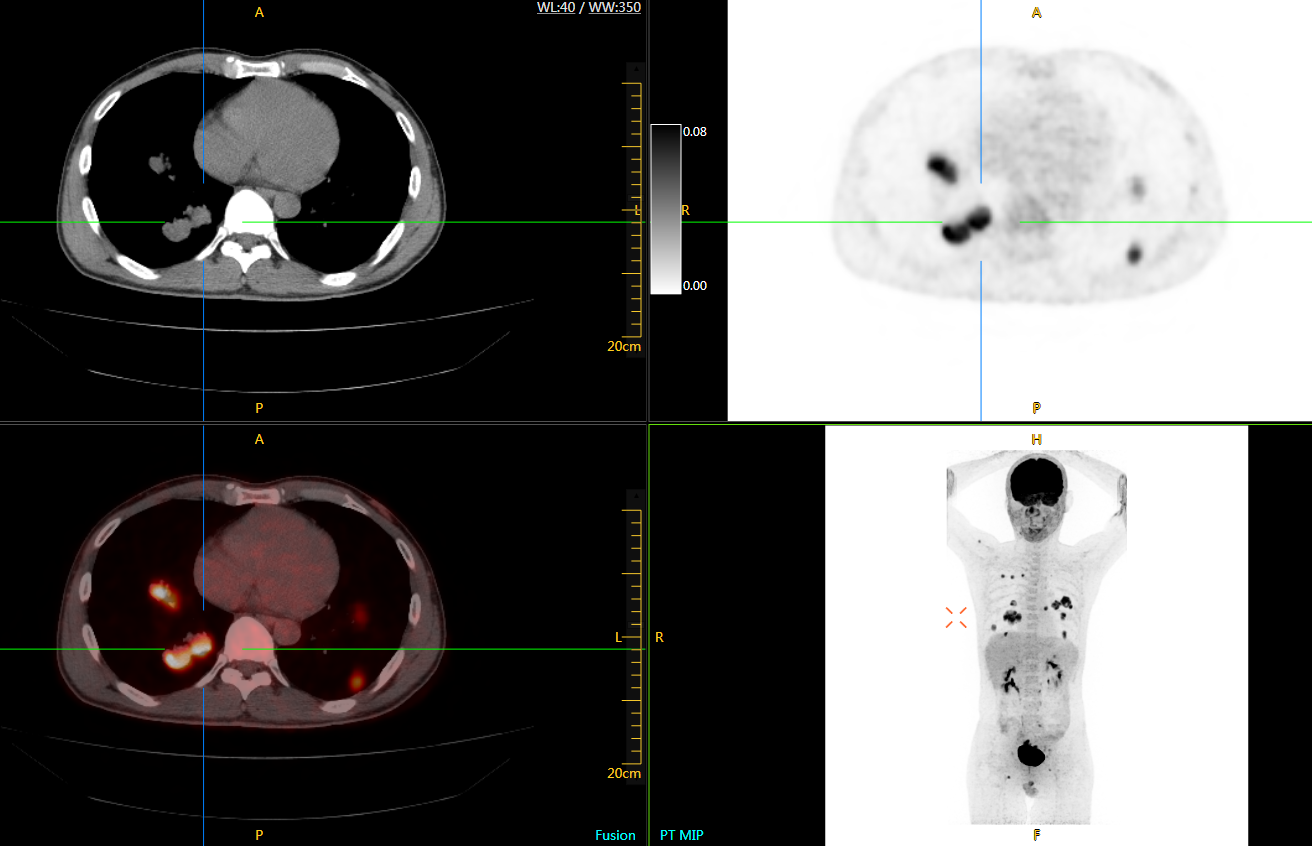

肺癌轉(zhuǎn)移及復(fù)發(fā)

患者男性,66歲,七年前發(fā)現(xiàn)右肺肺癌,其間手術(shù)兩次,共切除兩個肺葉,復(fù)查;

診斷意見,回腸轉(zhuǎn)移,右肺殘留部復(fù)發(fā)